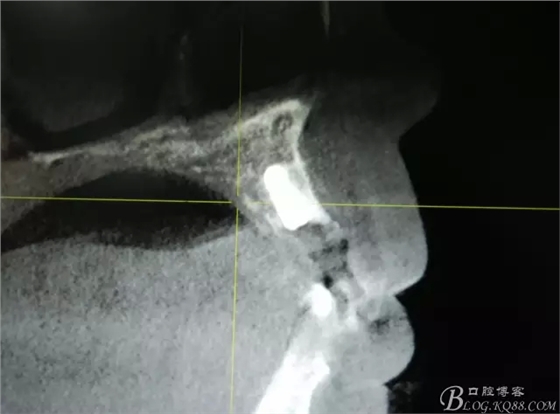

圖2.CBCT的三維成像及縱剖面、水平面影像